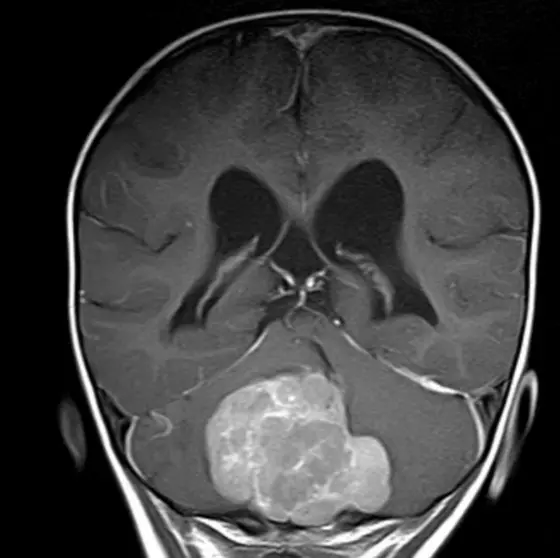

MRT Image of a medulloblastoma in the cerebellum of a child.

Medulloblastoma is one of the most common malignant tumors of the central nervous system (CNS) in children and adolescents. It develops in the area of the cerebellum, which is responsible for movement coordination, among other things. Medulloblastomas enlarge rapidly, often grow into surrounding tissue and can also form metastases. The wide variety of this tumor group also makes it difficult to find the right treatment.